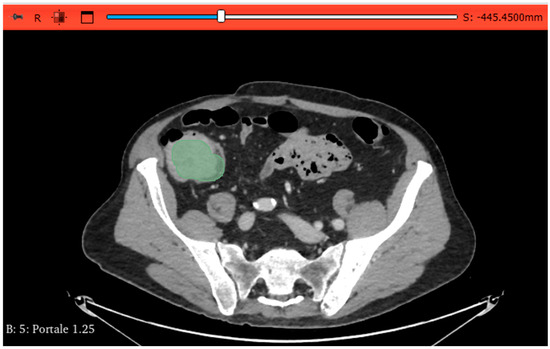

Prediction of Microsatellite Instability in Colorectal Cancer Using Two Internally Validated Radiomic Models

by Antonio Galluzzo, Ginevra Danti, Linda Calistri, Diletta Cozzi, Daniele Lavacchi, Daniele Rossini, Lorenzo Antonuzzo, Sebastiano Paolucci, Francesca Castiglione, Luca Messerini, Fabio Cianchi and Vittorio Miele

Objectives: To develop two different radiomic models based on preoperative contrast-enhanced computed tomography (PP CT) to predict microsatellite instability (MSI) in patients with colorectal cancer (CRC) before surgery. Methods: PP CT scans of 115 CC patients were segmented using 3DSlicer (v5.6.1). Model I [...] Read more.

Objectives: To develop two different radiomic models based on preoperative contrast-enhanced computed tomography (PP CT) to predict microsatellite instability (MSI) in patients with colorectal cancer (CRC) before surgery. Methods: PP CT scans of 115 CC patients were segmented using 3DSlicer (v5.6.1). Model I included images from three different scanners (GE, Siemens, Philips), while Model II used only one scanner (GE). For Model I, 80 patients were used for training and 35 for internal validation; for Model II, 46 and 24 patients were used, respectively. Data on sex, age, tumour location, and MSI genomic status were collected. A total of 107 radiomic features (RFs) were extracted, and 30 and 35 RFs were identified as relevant for Models I and II, respectively, using the t-test or Mann–Whitney test (p < 0.05). The most robust RFs were selected using the LASSO regression method. Both models were internally validated. Results: Model I, based on 2 RFs and 1 clinical feature (LOCATION) achieved an AUC of 0.76 (95% CI: 0.65–0.87) in the training cohort and 0.74 (95% CI: 0.56–0.92) in the validation cohort. Model II, based on 3 RFs, achieved an AUC of 0.85 (95% CI: 0.73–0.96) in the training cohort and 0.72 (95% CI: 0.50–0.94) in the validation cohort. Conclusions: Both radiomic models showed good performance in distinguishing between MSI and non-MSI tumours, potentially reducing the need for invasive histological testing and improving treatment timing. Despite achieving a higher AUC, Model II showed signs of overfitting when compared to Model I, which incorporated two RFs and one clinical feature (LOCATION). Radiomics may function as a non-invasive preoperative screening tool to inform decisions regarding MSI testing and treatment. Building radiomic models on larger, more diverse datasets is preferable to enhance generalizability and reduce overfitting. Full article

(This article belongs to the Section Abdominal Imaging)